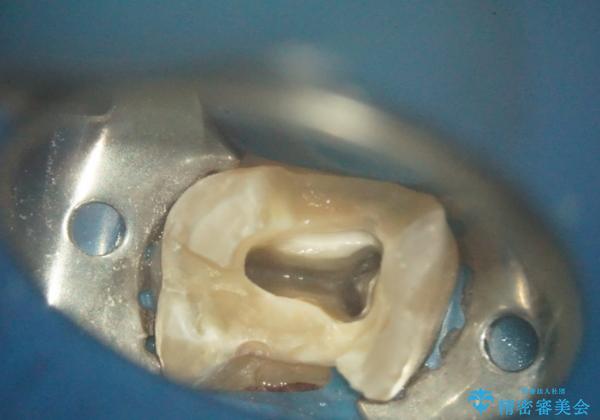

- 古い詰め物を除去し、腐ってしまった神経を顕微鏡下で丁寧に処理する

→根管治療完了後、土台を築造し、かぶせ物を製作してかみ合わせを回復する

すでに感染が根の先端まで及んでいたため、かなり強い痛みがありましたが、丁寧に根管治療をすることで内部を可及的に無菌化し、痛みが消失しました。